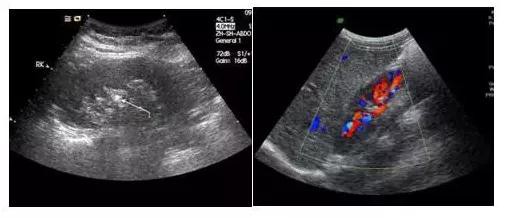

众所周知,B超检查是体验中必不可少的项目,它可直观而清晰地发现人体各脏器如肝、肾、胰腺、甲状腺、乳腺、膀胱等的多种病变。B超又有黑白超和彩超之分,有时我们做黑白B超检查,有时是彩色B超。其实对患者来说除了两者价格有高低外,对它们之间的差别并不十分清楚。是越贵越…